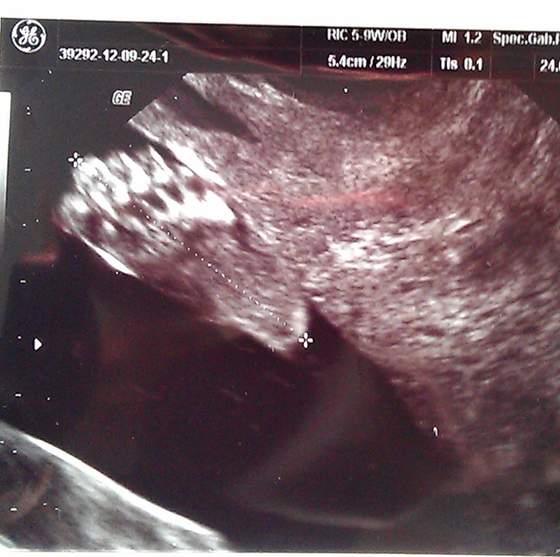

Kochane lutóweczki my już po wizycie. Dzieć ruchliwy :-) serduszko bije jak szalone jest git :-) Niestety nie udało się zobaczyć płci bo maluch ma cały czas pępowinę między nóżkami. USG miałam robione i z góry i z dołu i niestety nie dało się nic zobaczyć:-( Maleństwo jest ułożone w pionie czyli główka pod pępkiem a nóżki na mamusiowym pęcherzu (a ja się dziwię, że latam co chwilę sikać :-D) Piękny to widok jak maleństwo sobie fika nóżkami :-) Następną wizytę mam 24.10 ale między 15 a 30.10 muszę się zapisać do innego lekarza na połówkowe bo moja nie ma jakieś potrzebnego sprzętu.

A i jak robiła mi USG od dołu to uchwyciła piękny obrazek :-) same zobaczcie i powiedzcie, czyż nie jest piękna? :-)